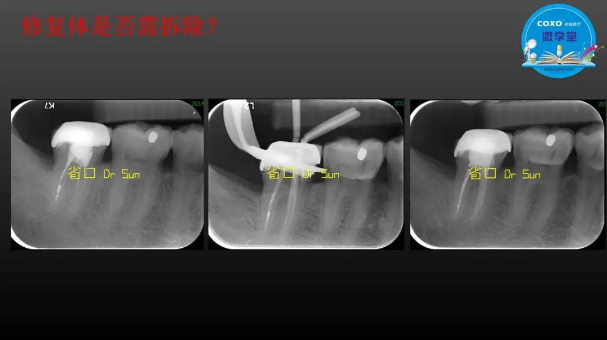

主講:孫書昱

主任醫(yī)師,牙體牙髓副主任, 廣東省口腔醫(yī)院牙體牙髓科 主任醫(yī)師。2003年碩士研究生畢業(yè),研究方向?yàn)檠荔w牙髓病學(xué),擅長(zhǎng)于牙體牙髓病的診斷、齲齒、牙髓炎、根尖周病的治療以及前牙美容修復(fù)。